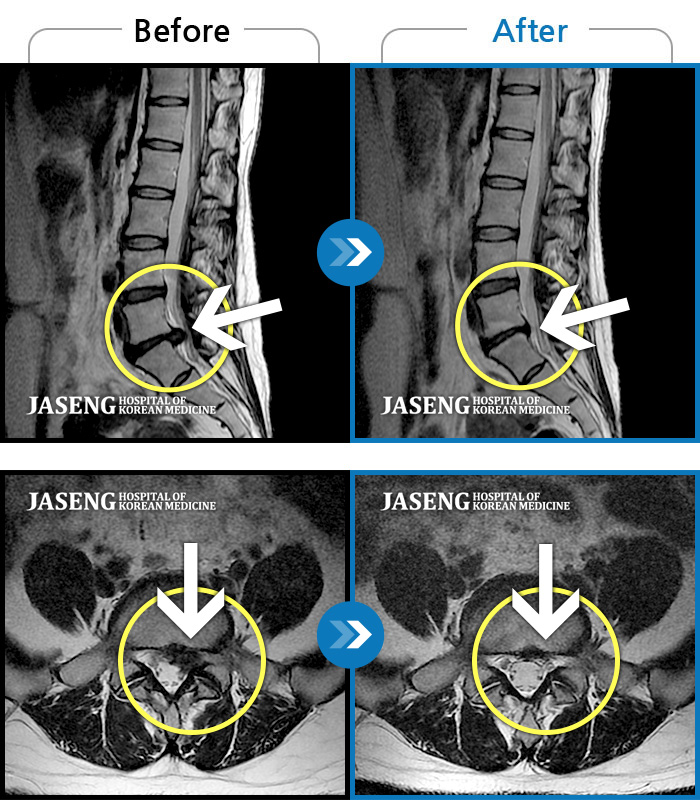

허리디스크

일산 · 김진수 원장

처음 내원 시 우측 엉덩이가 많이 아프고, 우측 다리로 근력 및 감각 저하도 있어 발목 움직임이 원활치 못했으며, 야간통으로 잠도 못 자고 통증 심하여 정상적인 활동이 힘든 상태셨습니다.

촬영시기

2023.12.04 ~ 2024.06.04

2024.06.21